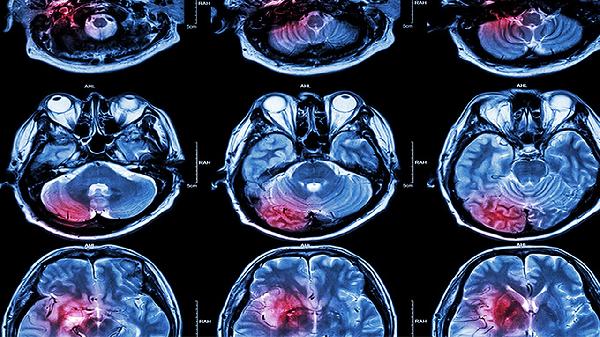

脑外伤三慢一快指患者出现思维迟缓、动作迟缓、言语迟缓与心率增快的典型症状组合,常见于中重度颅脑损伤。